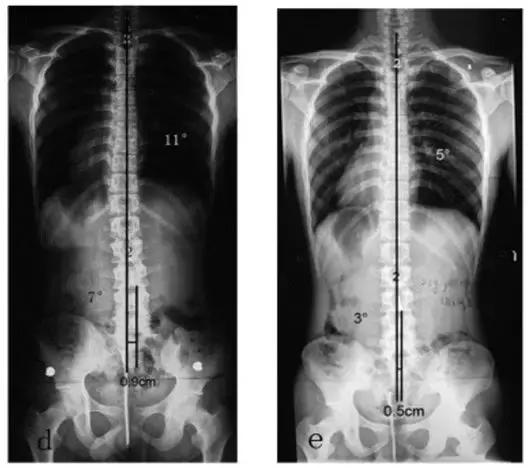

可以看下面这张图(图文引用于文献【1】),患者为右侧L5-S1间盘突出,术前脊柱侧弯非常严重!上半身重心偏移也非常严重!

下方左图是术后即刻的,可以看到侧弯已经大部分恢复了!下方右图是术后2.5年的,侧弯基本上完全恢复!